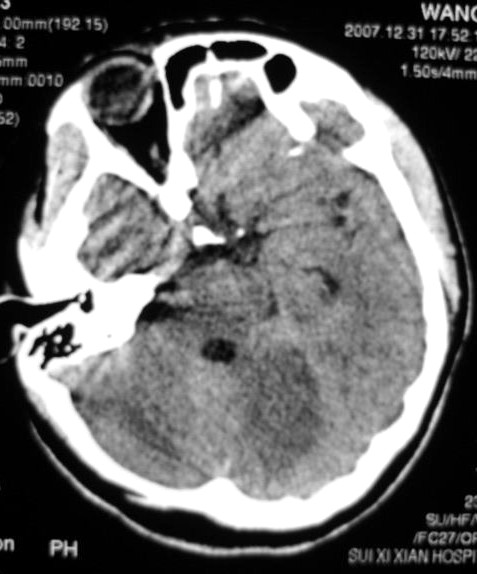

以下是引用zjzjr在2008-2-19 15:45:00的发言:[br]左侧小脑缺血性脑梗塞,基底节区脑梗塞,强烈建议血管造影,除外烟雾病。

以下是引用玉真在2008-2-19 17:46:00的发言:[br]多发性脑梗塞,不知病人是否有风心或先心病史